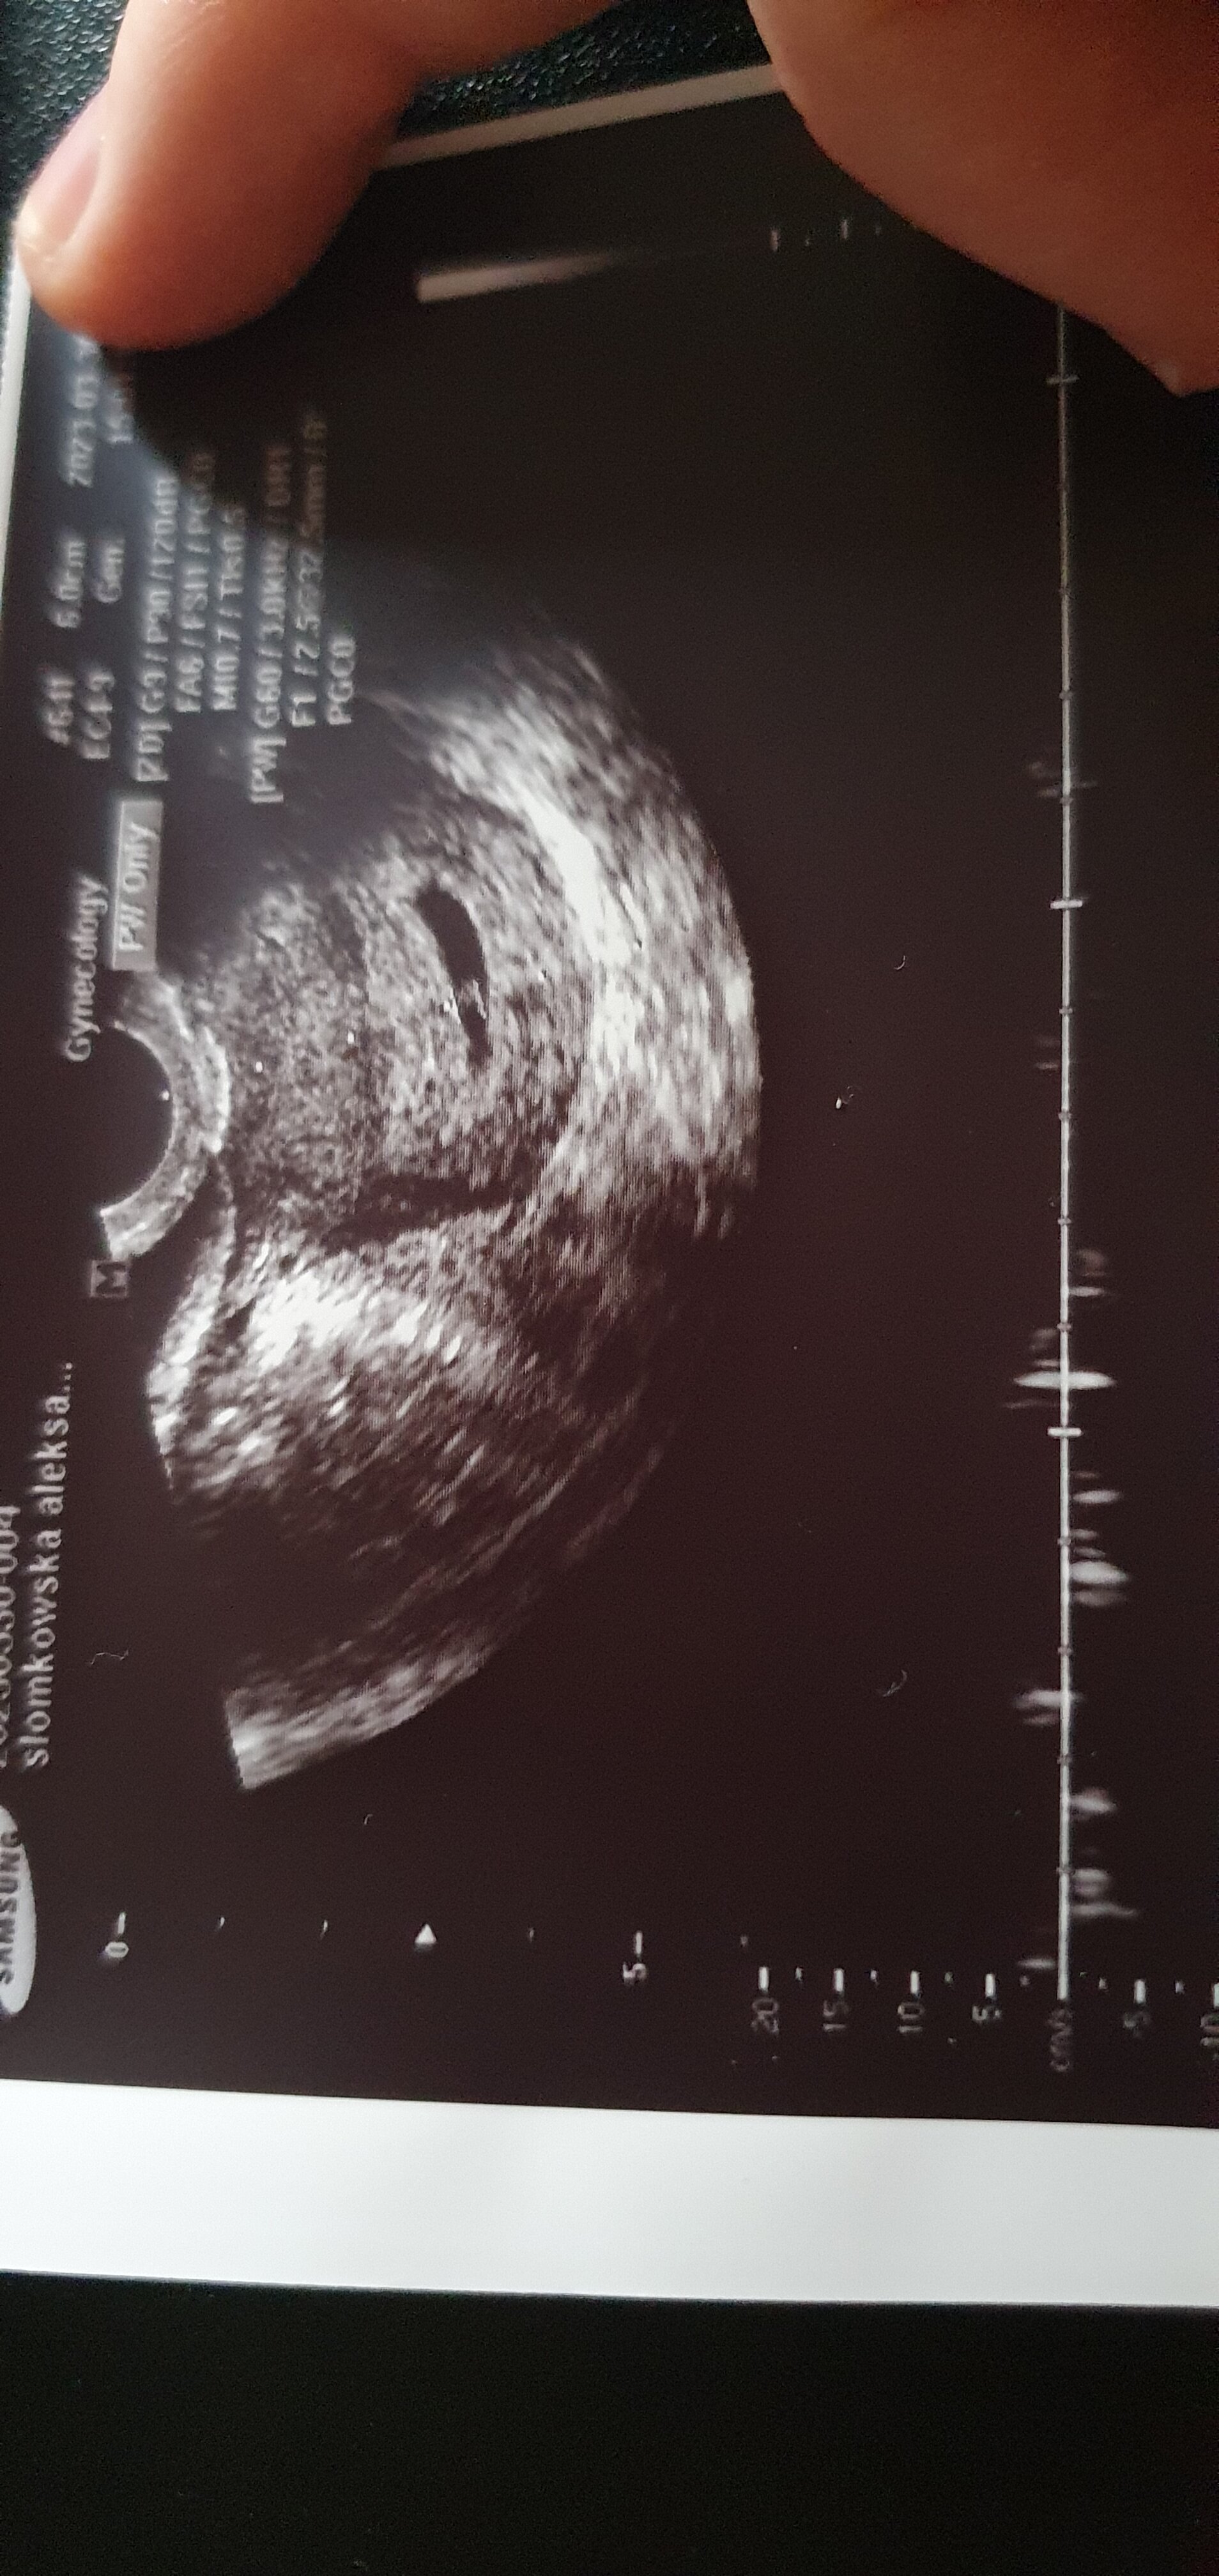

Wróciłam, trochę się przeciągnęło... Na USG jest pęcherzyk z zarodkiem 6,7mm- wymiar odpowiada idealnie terminowi który wyliczyłam- 6t+4.

Ale... żeby nie było tak pięknie... Mam krwiaka co prawda oddalonego od zarodka ale się ciągle opróżnia zamiast wchłaniać i jest sporym zagrożeniem dla ciąży. Kolejną wizytę mam w środę żeby zobaczyć czy zarodek się rozwija bo serce trochę za wolno bije-104/min.

Do tego skrzepy z rana były prawdopodobnie drugim pęcherzykiem ciążowym który był koło tego krwiaka i się nie utrzymał bo nadal mam jakieś tkanki które będą się musiały jakoś wydostać z macicy więc krwawień ciąg dalszy będzie...